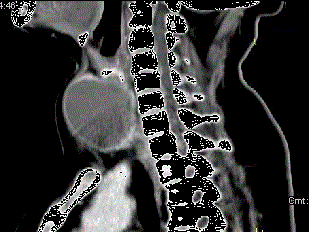

问题 女,56岁,发现颈部肿块一月余,CT如图所示,最可能诊断为 ( )

选项 A、甲状腺腺瘤 B、甲状腺脓肿 C、甲状腺乳头状癌 D、甲状腺原发淋巴瘤 E、甲状舌管囊肿

答案 A